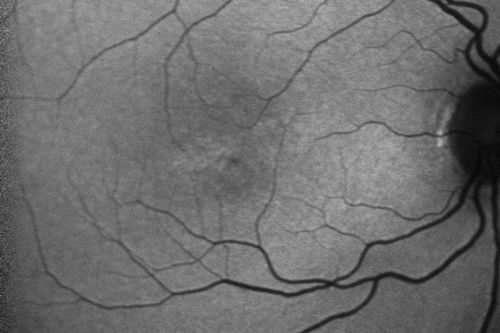

Macular Telangiectasis (Group 2a Juxtafoveal Telangiectasis) Decreased Fundus Autofluorescence

63-year-old woman has juxtafoveal retinal telangiectasis in both eyes.  She notices her vision a little worse with more distortion and change over the last six months.

VISUAL ACUITY:  OD 20/40,  OS 20/40.